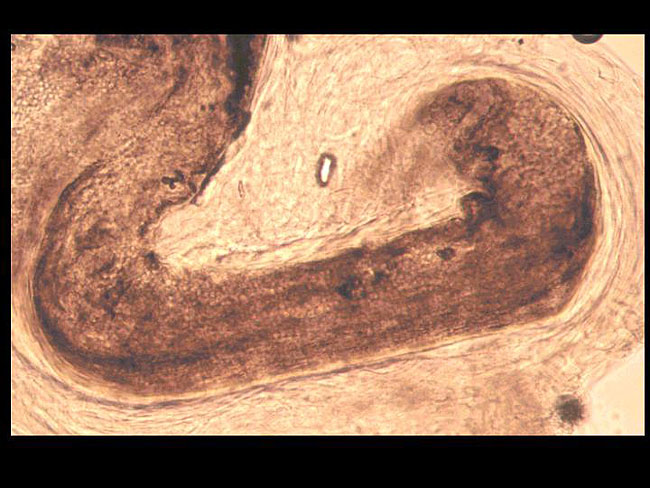

以前、このような症例を経験していたので、これは「blackdotringworm」(黒点状白癬)ではないかと考えました。さっそく診断のためにその黒点(真菌によって毛が切れたもの)をピンセットで引き抜いて、顕微鏡で見ると、やっぱり毛の中に丸い真菌の胞子が沢山見られました(写真)。

これで診断は確定です。真菌を培養してみると、黄色い色素を出す毛羽だった菌集落(写真)で、菌成分の顕微鏡所見(写真)から、「トリコフィートン・トンスランス」であることが同定できました。